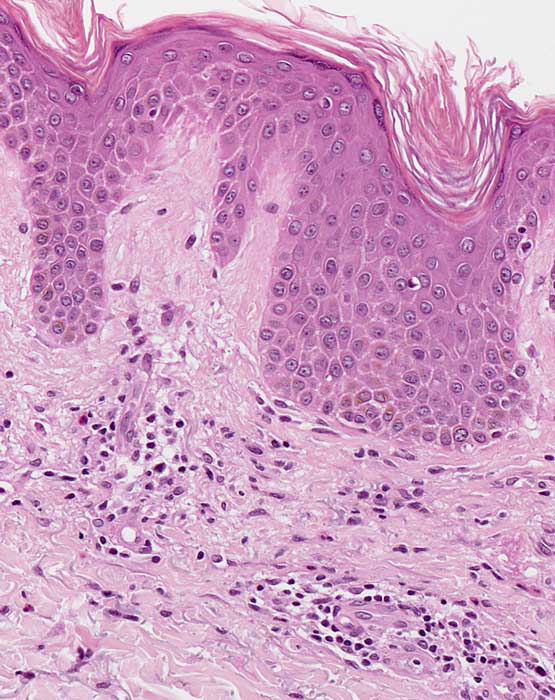

Entzündliche Hautreaktion mit Spongiose. Die Spongiose ist definiert als interzelluläres Ödem von Epidermis und/oder Adnexepithel, erkennbar an der Verbreiterung der Interzellularräume im Epithel. Bei gering ausgeprägter Spongiose stehen benachbarte Keratinozyten über verlängerte Interzellularbrücken noch miteinander in Kontakt, während bei stärkerer Ausprägung die desmosomalen Verbindungen dem Ödem nicht mehr standhalten und rupturieren, so dass sich die Zellen voneinander lösen und ein intraepitheliales Bläschen (spongiotisches Bläschen) entsteht. Dieser Prozess ist Ausdruck einer Entzündungsreaktion, die in der Regel durch Lymphozyten, seltener durch eosinophile oder neutrophile Granulozyten vermittelt wird. Die beteiligten Zellen sind im betroffenen Epithel (lymphozytäre Exozytose) und in der oberen Dermis nachweisbar. Verteilungsmuster und Zusammensetzung der Entzündungszellen können einen Hinweis geben auf die Ursache des spongiotischen Reaktionsmusters. Man unterscheidet klinisch und histopathologisch unterschiedliche Stadien (akut-subakut-chronisch).

Histologisch zeigen akute Ekzeme eine ausgeprägte Spongiose mit intraepithelialer Bläschenbildung, eine Parakeratose und Krustenauflagerungen, im chronischen Stadium eine Verminderung der Spongiose, eine Akanthose und Hyperparakeratose. Bei alten Läsionen können Parakeratosehügel und eine Epidermishyperplasie der einzige Hinweis auf eine spongiotische Dermatitis sein. Die Epidermishyperplasie ist teilweise eine Folge des chronischen Reibens und Kratzens der juckenden Haut. Das Entzündungsinfiltrat in der oberen Dermis besteht aus Lymphozyten und Histiozyten, zum Teil auch aus neutrophilen und eosinophilen Granulozyten. In der Epidermis dominieren Lymphozyten (lymphozytäre Exozytose). Akute, subakute und chronische Veränderungen können beim gleichen Patienten nebeneinander vorkommen.

• Verdickte Epidermis (Akanthose)

• Spongiose (interzelluläres Ödem der Epidermis)

• Spongiotische Vesikel (intraepitheliale Bläschenbildung)

• Parakeratotische Verhornung (Verhornte Zellen mit erkennbaren Zellkernen)

• Ödem der papillären Dermis (Aufhellung)

• Oberflächlich dermales perivaskulär betontes Entzündungsinfiltrat

• Lymphozyten, Histiozyten, neutrophile und eosinophile Granulozyten